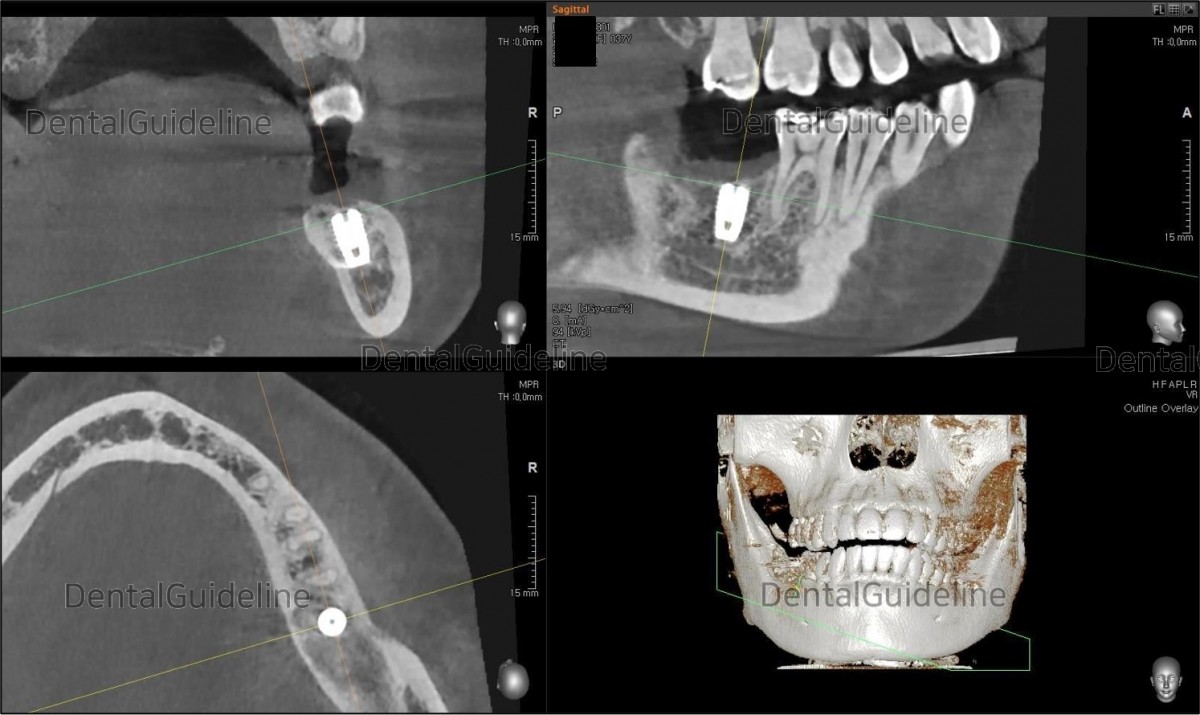

3. CBCT shows the root rest.

3. The root remnant was removed at the 2nd molar area on the right side, and site preparation was performed.

4. Implant was placed (Arum-Dentistry Co. NB Ø5/L8.5mm, 40Ncm).

8. CBCT scan image.